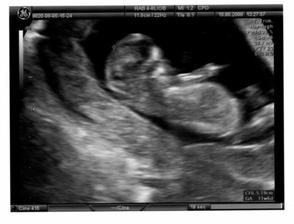

Ve středu 20.8.08 byla maminka s tatínkem v kině na muzikálu Mamma mia a já (malé miminko) jsem pařilo v bříšku až do rána. A na další den jsem se fotilo u pana doktora, ale o tom nic nevím, protože jsem po tak náročné noci celý den spinkalo. Alespoň si mě mohli pěkně vyfotit na 3D ultrazvuku. Změřili mi hlavičku a prý jsem se tatínkovi poved i když mě dělal po tmě

🙂.

Zatím mám takových 22 - 24 cm a vážím okolo 800 g.

Do obrazu se mi vejde už jen hlavinka.